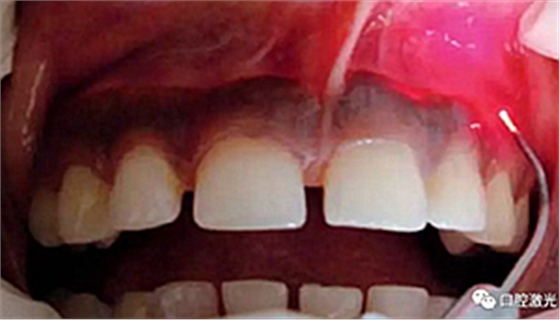

术后即刻

患者术后无明显疼痛不适,没有出现大量出血、感染或结痂现象。整个恢复过程较为顺利。患者接受度高,治疗效果明显。